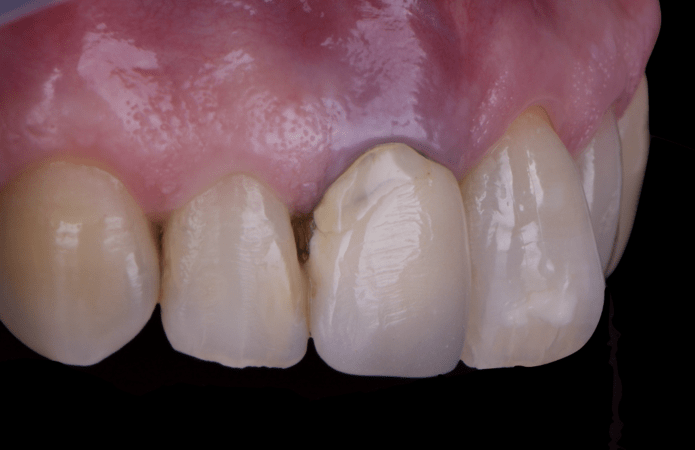

After an appropriate healing period, the definitive prosthesis was planned and delivered. A screw-retained zirconia crown was fabricated to ensure long-term durability, optimal esthetics, and retrievability. Zirconia was selected for its mechanical strength and excellent esthetic properties, blending seamlessly with the adjacent natural dentition in both form and color.

The final crown was designed to maintain the gingival architecture that had been shaped by the provisional. Special attention was paid to the emergence profile, contact points, and translucency to achieve harmony with the patient’s smile. The definitive restoration provided functional stability and esthetic integration, fulfilling the patient’s expectations for a fixed and natural solution.

This case demonstrates the benefits of combining immediate implant placement with simultaneous guided bone regeneration and connective tissue grafting in a high-esthetic area. The use of the N1 system and the “one abutment one time” protocol facilitated predictable healing and minimized disturbance of peri-implant tissues. Immediate provisionalization contributed significantly to soft tissue shaping and patient satisfaction throughout the process.